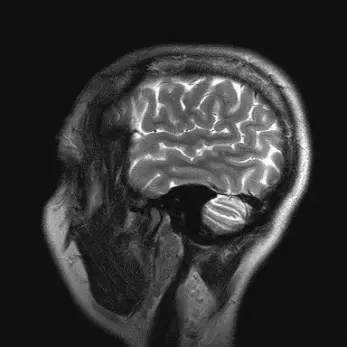

Врачи сызранской ЦГРБ развенчали пять мифов о мозге

Мозг - наименее изученный человеческий орган. Многие аспекты его работы остаются загадкой для ученых всего мира. Это рождает множество мифов, заявили в ЦГРБ Сызрани.